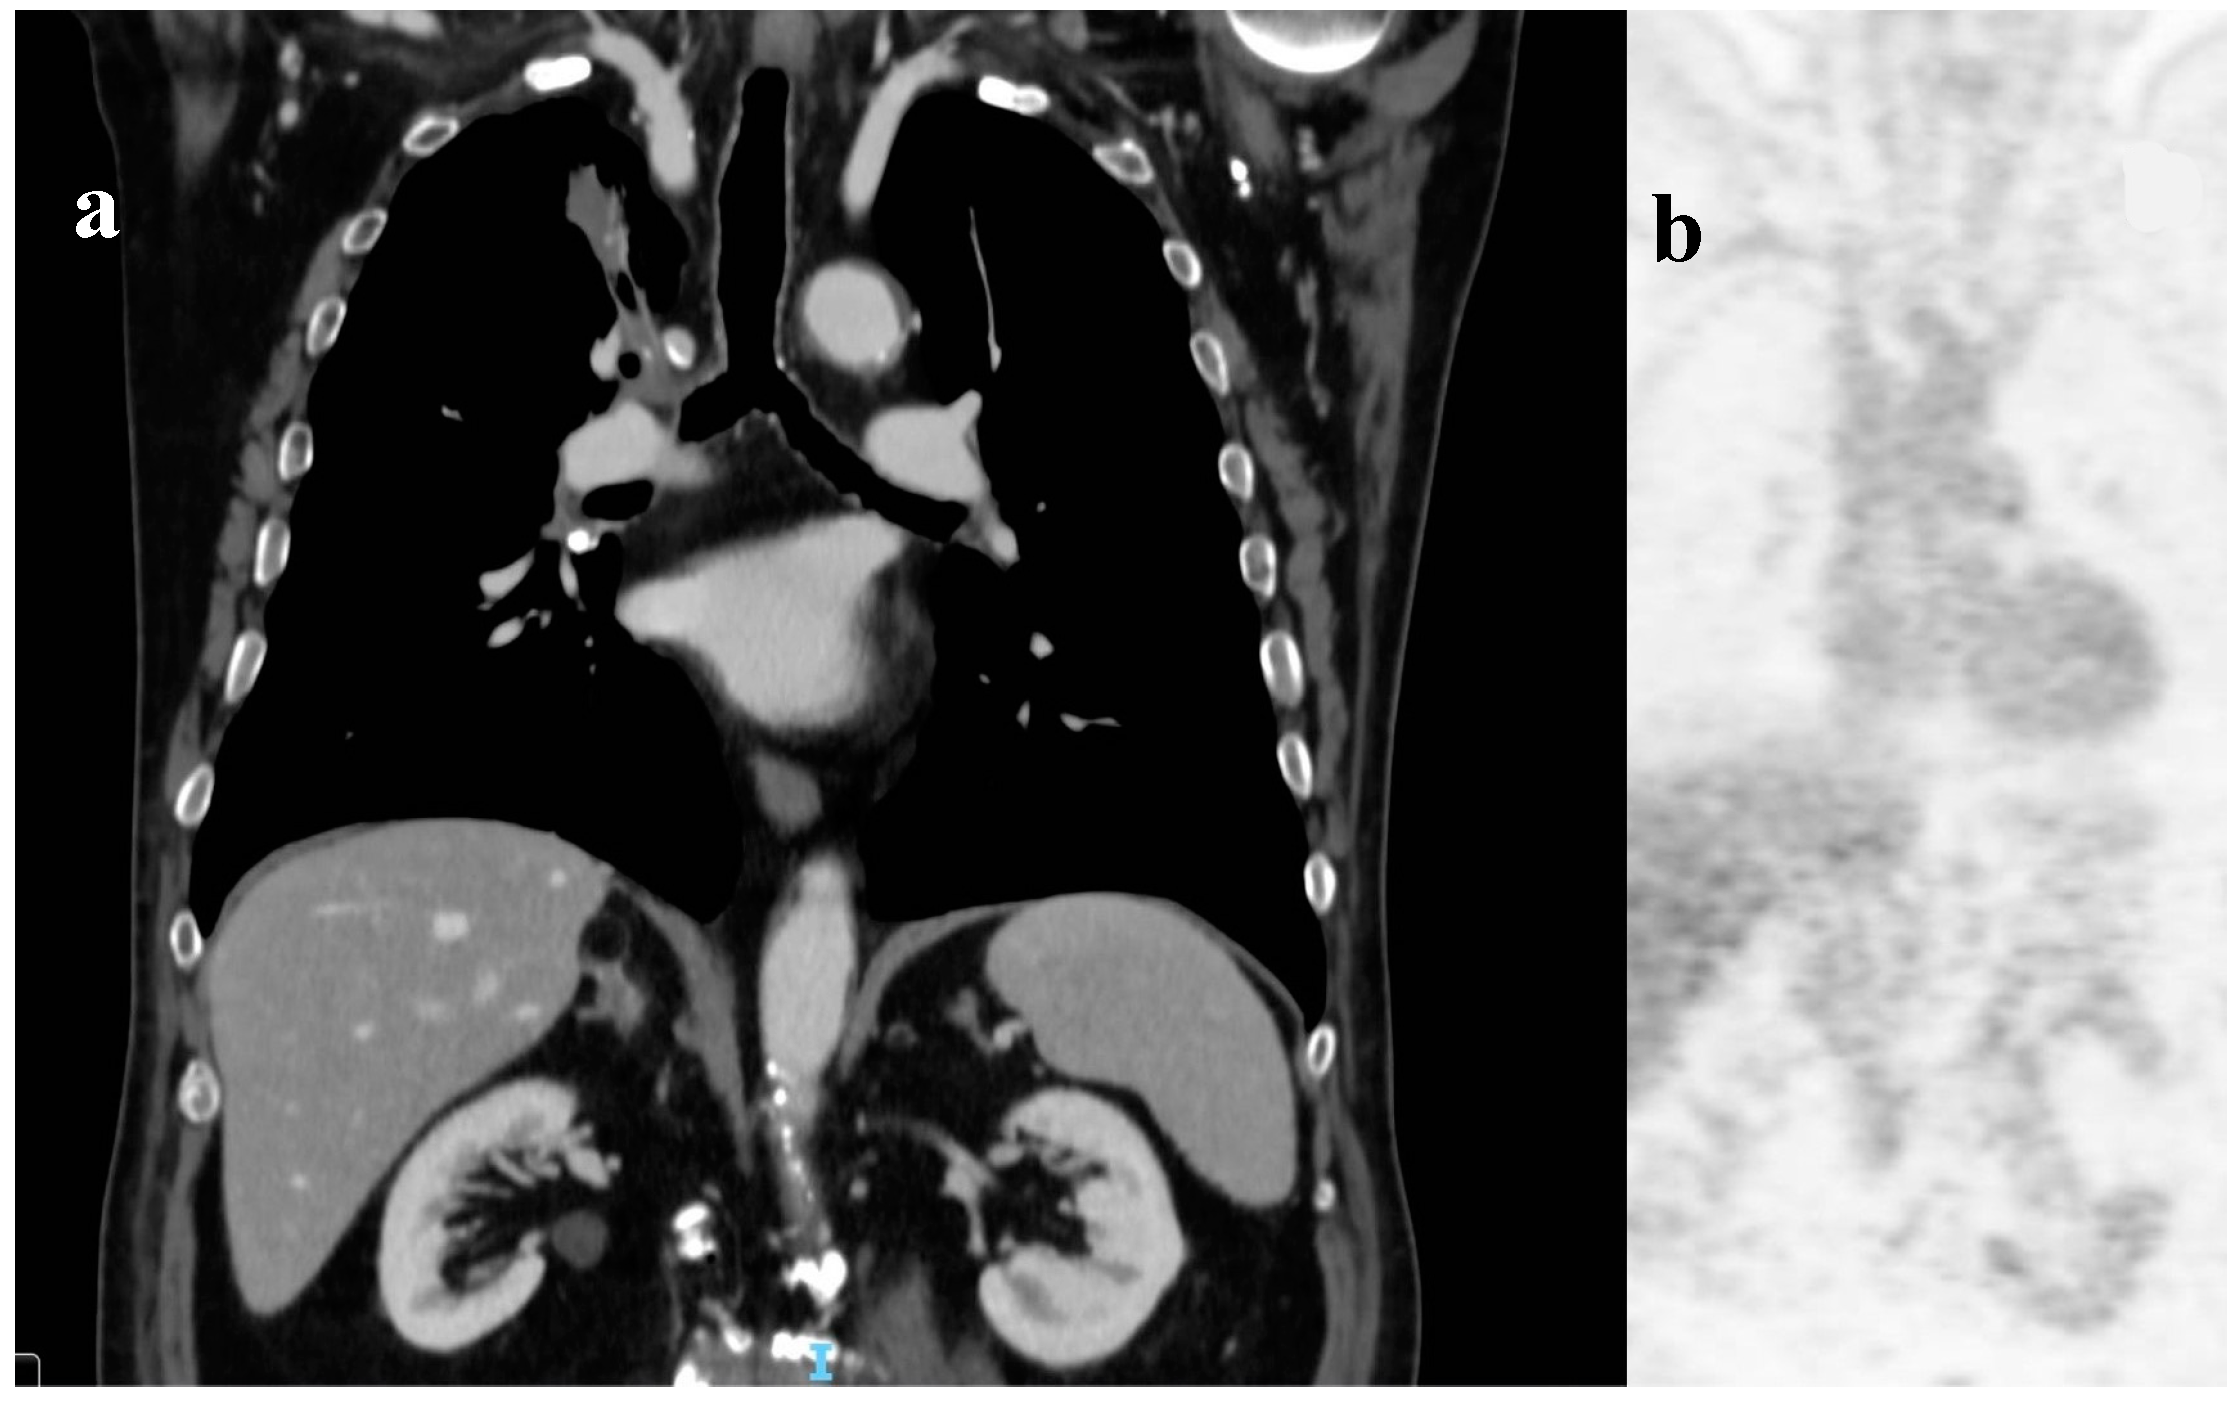

Magnetic resonance (MRI) of the brain was performed, reporting the presence of 3 brain lesions (one in the left frontal lobe of about 4 cm, the other 2 in the cerebellum right and left of about 2 cm) with oedema (Figure 1a-b-c). Moreover, an occipital bone lesion was reported.

Figure 1. Brain magnetic resonance at diagnosis. Legend: (a) right cerebellar lesion; (b) left cerebellar lesion; (c) left frontal lobe lesion.